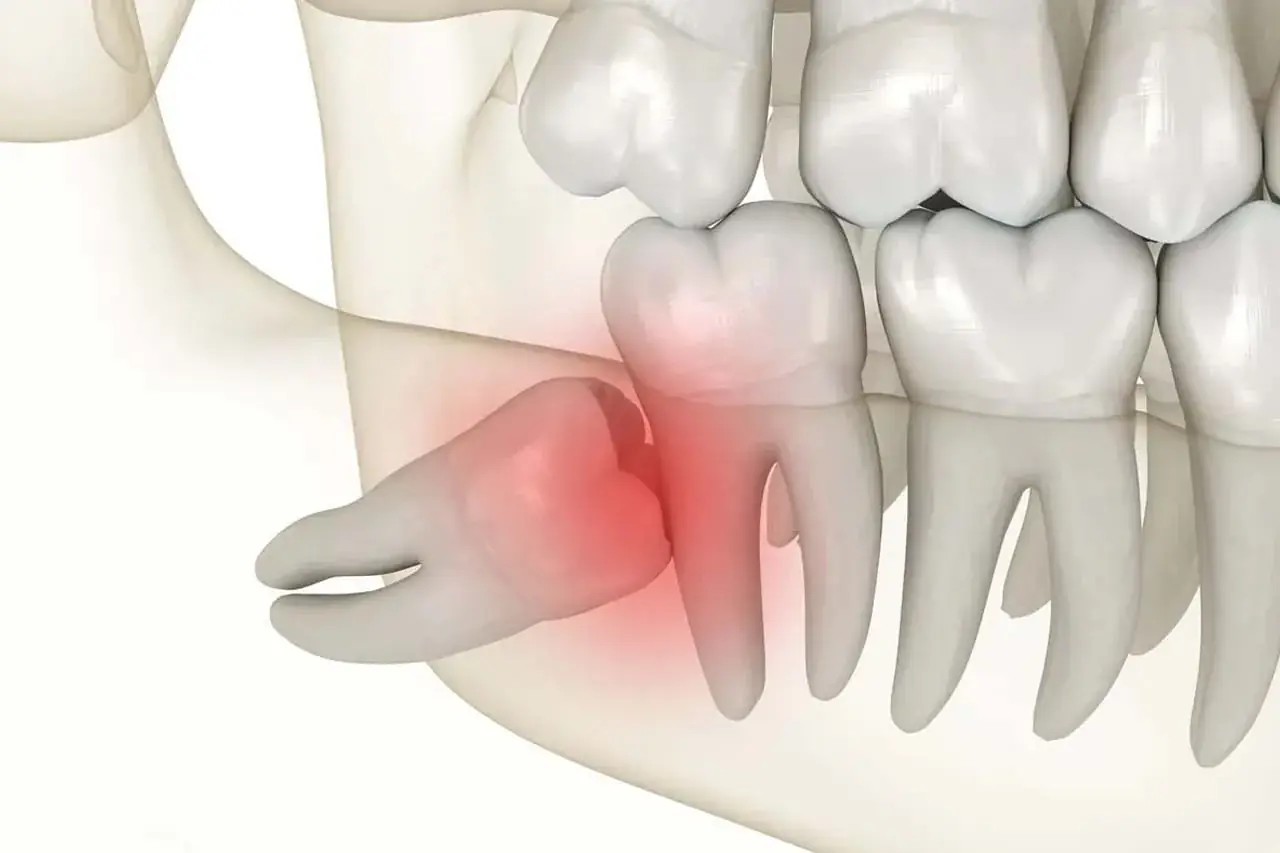

Gum Infections

Around partially erupted teeth leading to inflammation, pain and recurrent infections.

- Red, swollen and tender gums

- Recurrent pericoronitis

- Bad breath and taste

- Difficulty in maintaining hygiene